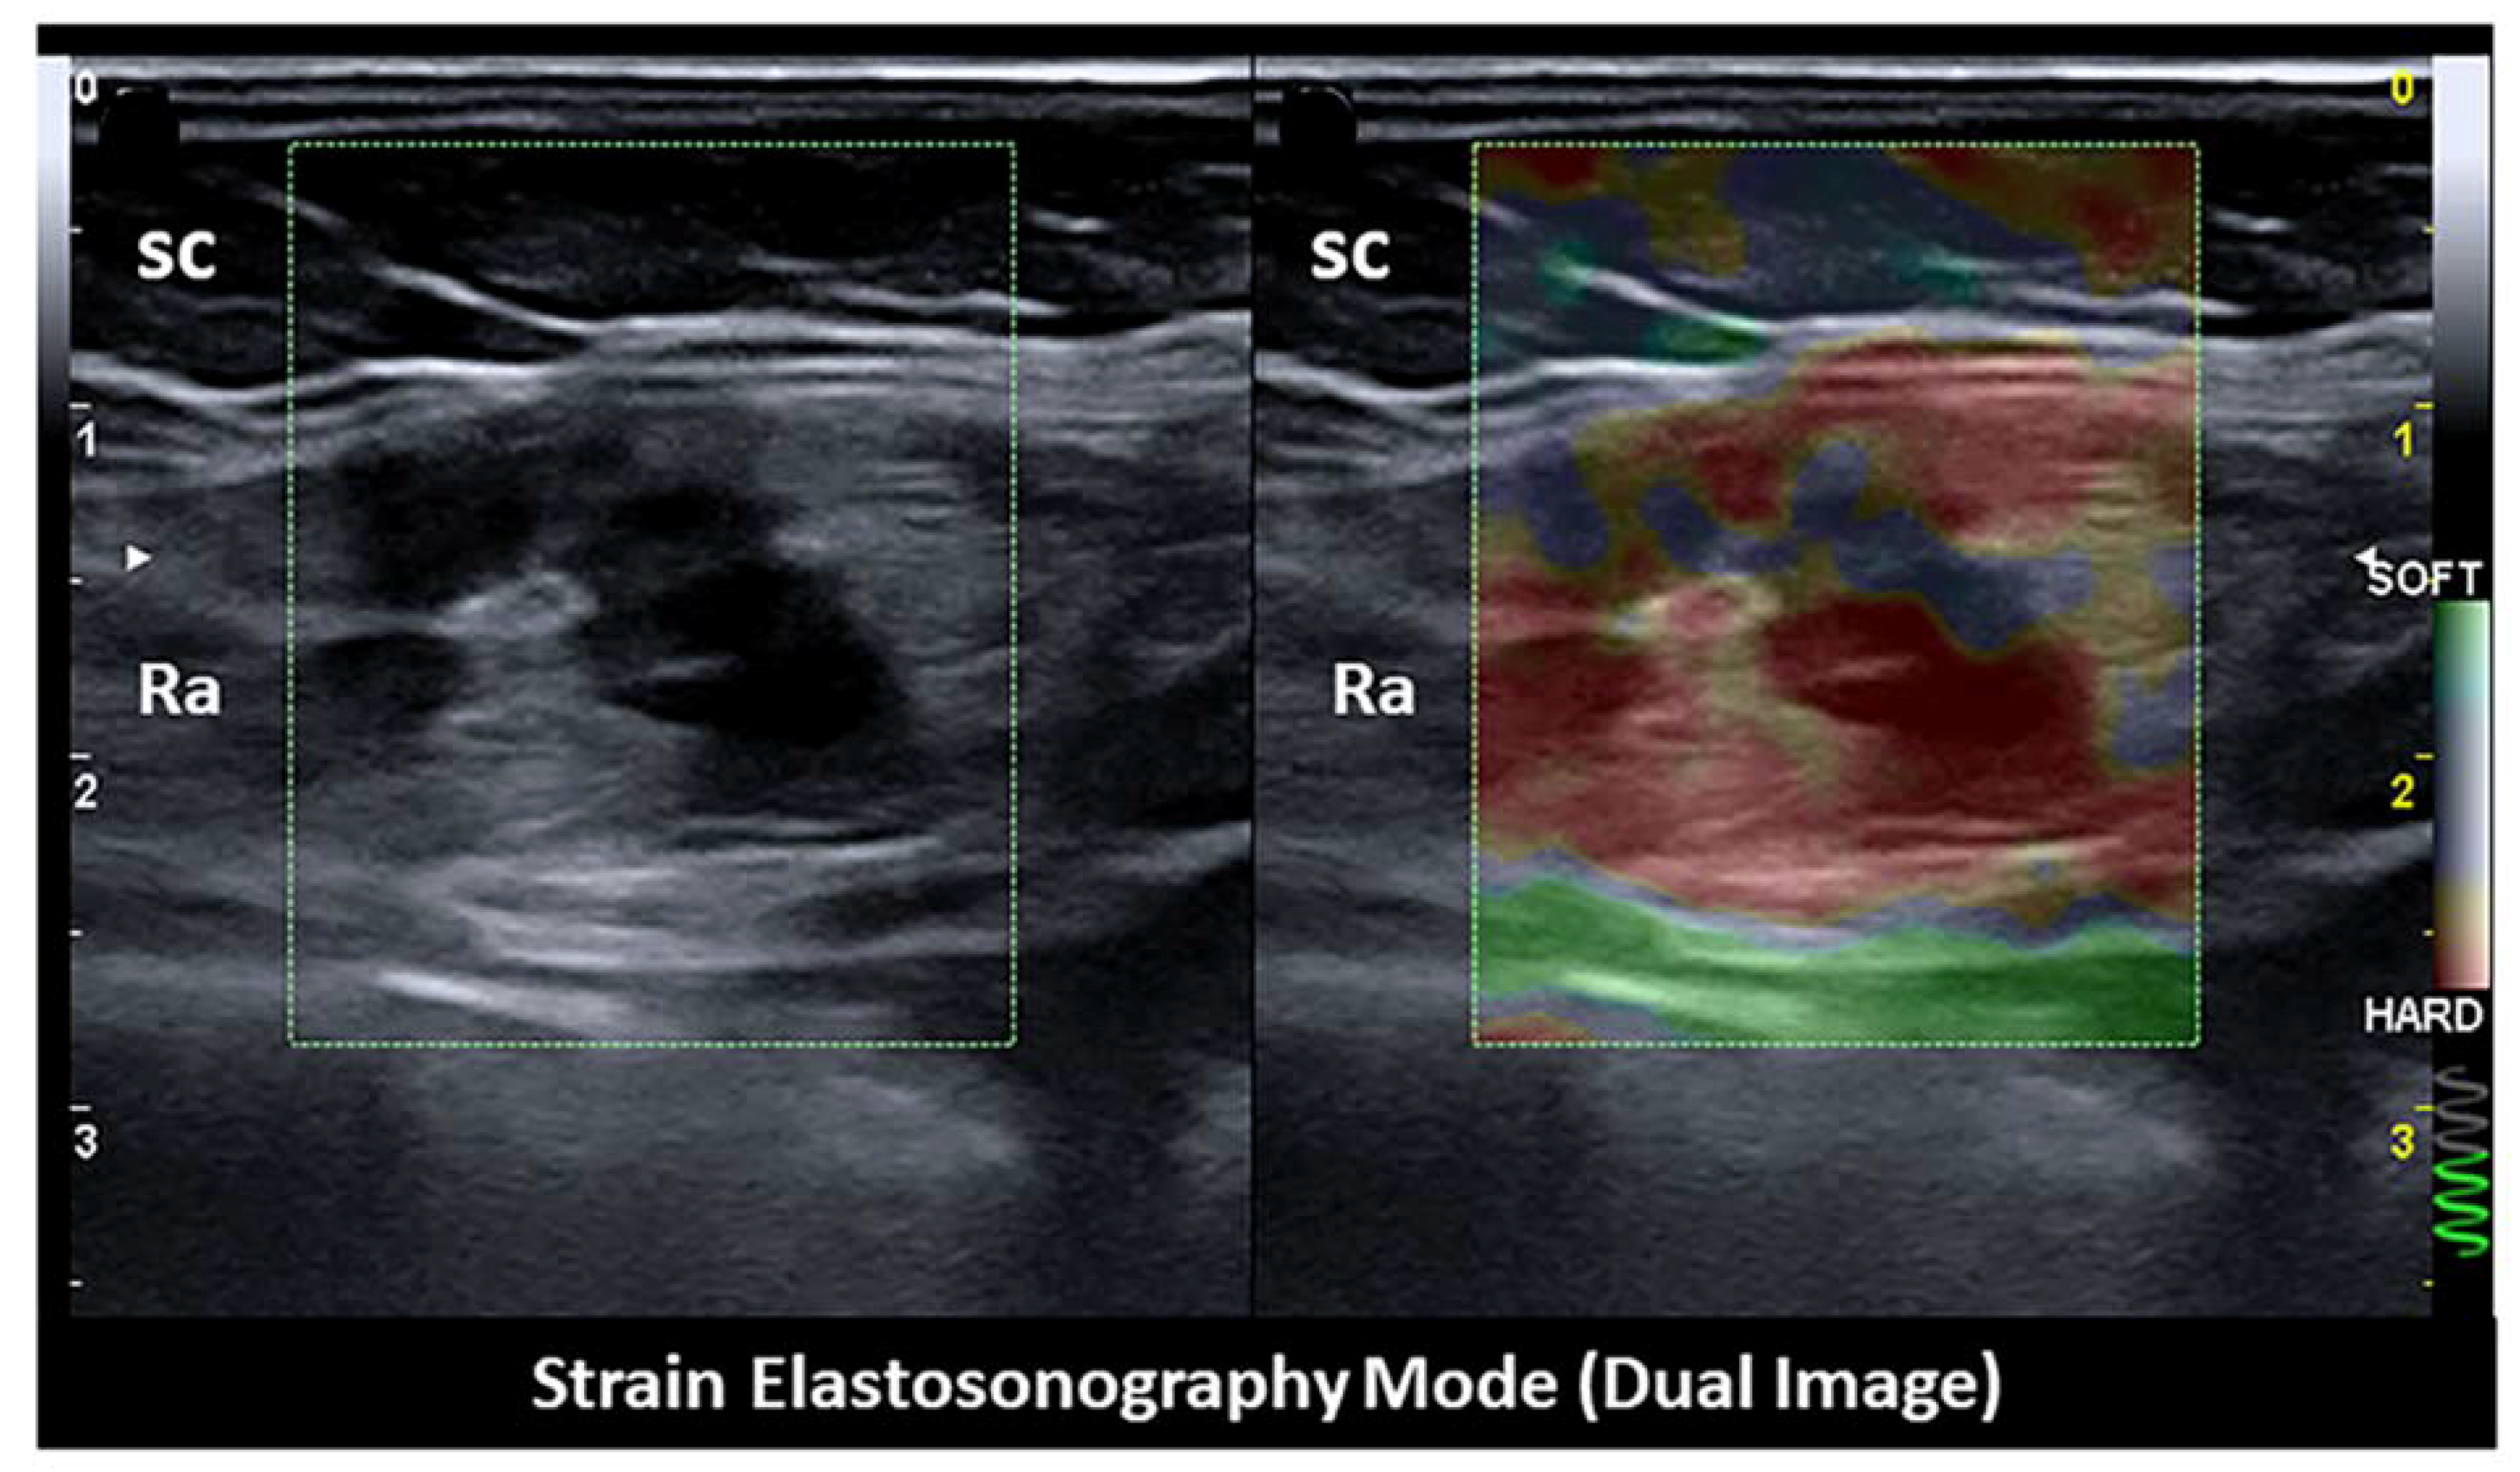

- Xie, M.; Zhang, X.; Zhan, J.; Ren, Y.; Wang, W. Potential role of strain elastography for detection of the extent of large-scar endometriosis. J. Ultrasound Med. 2013, 32, 1635–1642. [Google Scholar] [CrossRef]

- Viganò, P.; Ottolina, J.; Bartiromo, L.; Bonavina, G.; Schimberni, M.; Villanacci, R.; Candiani, M. Cellular Components Contributing to Fibrosis in Endometriosis: A Literature Review. J. Minim. Invasive Gynecol. 2020, 27, 287–295. [Google Scholar] [CrossRef]